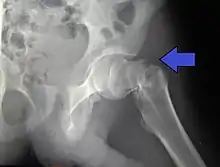

X-ray of a normal hip joint.

The hip joint is a ball-and-socket joint. The femur connects at the acetabulum of the pelvis and projects laterally before angling medially and inferiorly to form the knee. Although this joint has three degrees of freedom, it is still stable due to the interaction of ligaments and cartilage. The labrum lines the circumference of the acetabulum to provide stability and shock absorption. Articular cartilage covers the concave area of acetabulum, providing more stability and shock absorption. Surrounding the entire joint itself is a capsule secured by the tendon of the psoas muscle and three ligaments. The iliofemoral, or Y, ligament is located anteriorly and serves to prevent hip hyperextension. The pubofemoral ligament is located anteriorly just underneath the iliofemoral ligament and serves primarily to resist abduction, extension, and some external rotation. Finally the ischiofemoral ligament on the posterior side of the capsule resists extension, adduction, and internal rotation. When considering the biomechanics of hip fractures, it is important to examine the mechanical loads the hip experiences during low energy falls.